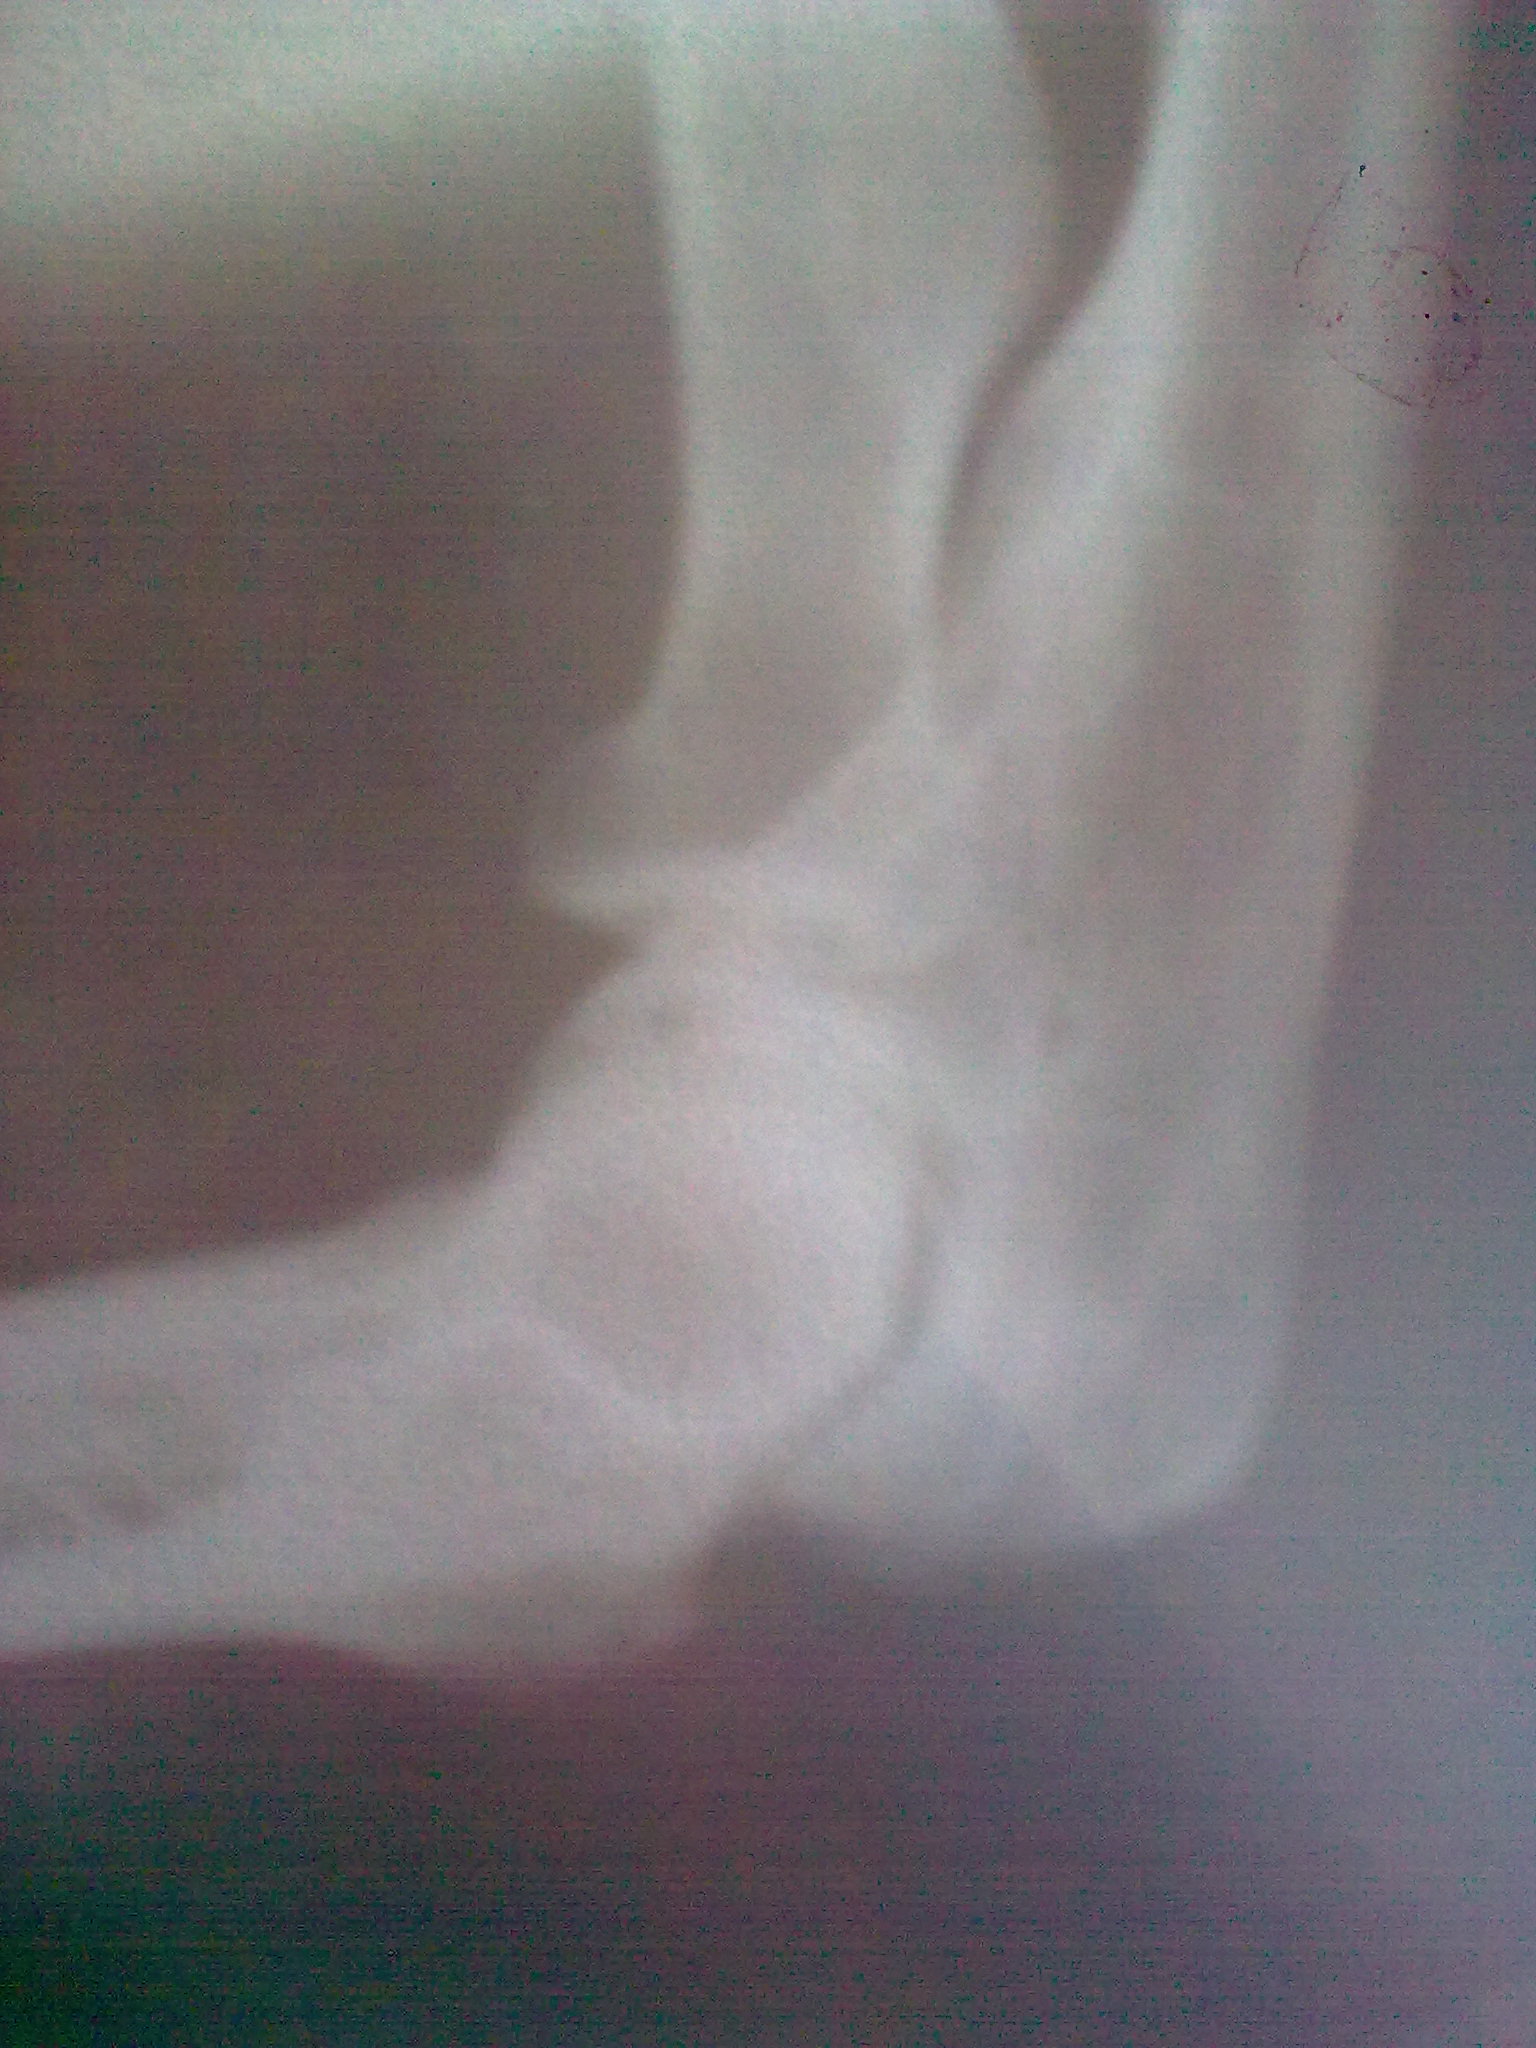

Добрый день!5 мес. назад получил травму правого локтевого сустава(вывих руки назад и вверх).Трещин и переломов нет.Ежедневными усилиями и ЛФК добился на сгибание 92 градуса на разгибание 155 градусов,а дальше не идет.Хотел Вашего совета ,делать операцию или поработать еще.Буду признательно благодарен за консультацию.Игорь,г.Каменец-Подольский.

• Кликните для загрузки файла Изображение 014.jpg

456KB (466954 bytes)